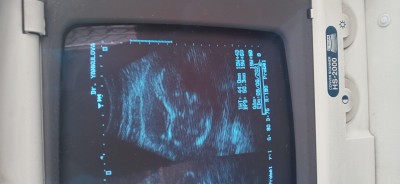

Deneyimli anneler acaba tahminde buluna bilirmisiniz pozisyonu uygun degil di doktor bisey diyemedi

Gebelik haftası 19+5

Bu nasıl usg cihazi hicbisey belli degl ki canim yoksa net soylenirdi suan bence

İlk fotoda bebek yüz üstü duruyor yani pozisyonu doğru değil bacak arası hiç gözükmüyor canım belki Dr bu yüzden söylememiştir yanlış tahmin de bulunmasın diye

Evet pozusyon uygun degil